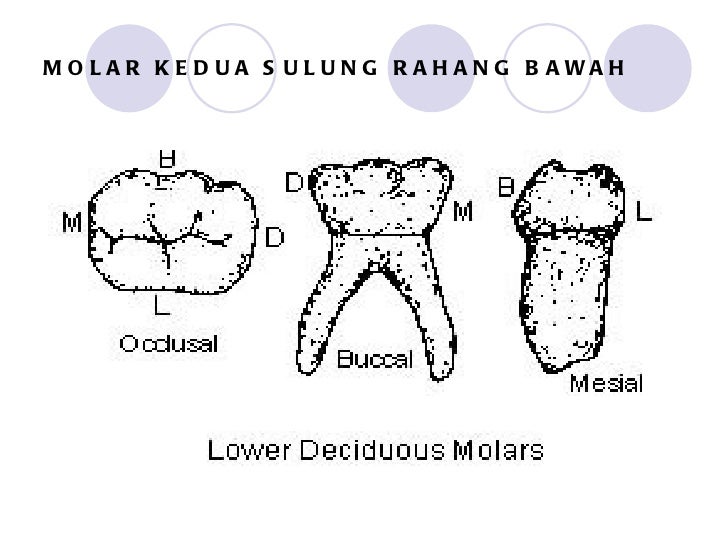

Morfologi gigi sulung2

Morfologi gigi sulung2

Morfologi gigi sulung2

Morfologi gigi sulung2